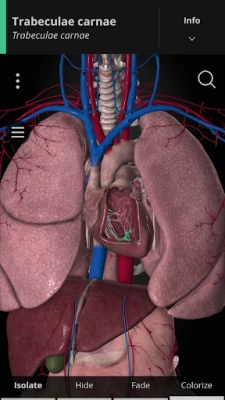

Using our cutting-edge 3D model, which is one of the most detailed in the world, ANATOMYKA allows you to get up close with human anatomy in all its breathtaking complexity on more than 13,000 anatomical structures with more than 500 pages of medical descriptions. Now in English, Spanish, Italian, Polish, Russian, Czech, Slovak and Hungarian localization.

In the ANATOMYKA app, each anatomical system, organ and part is accompanied by detailed information about its structure, hierarchy, regions, including information about organs, clinical notes, related organs (vascular supply, innervation, syntopy) and a general description.

Color-coded organs allow users to view high-resolution anatomical structures supplemented by informative descriptions from a comprehensive textbook ‘Memorix Anatomy’. These are arranged into a proper anatomical hierarchy, meaning learning is structured and easy to understand.

Color-coded organs allow users to view high-resolution anatomical structures supplemented by informative descriptions from a comprehensive textbook ‘Memorix Anatomy’. These are arranged into a proper anatomical hierarchy, meaning learning is structured and easy to understand.